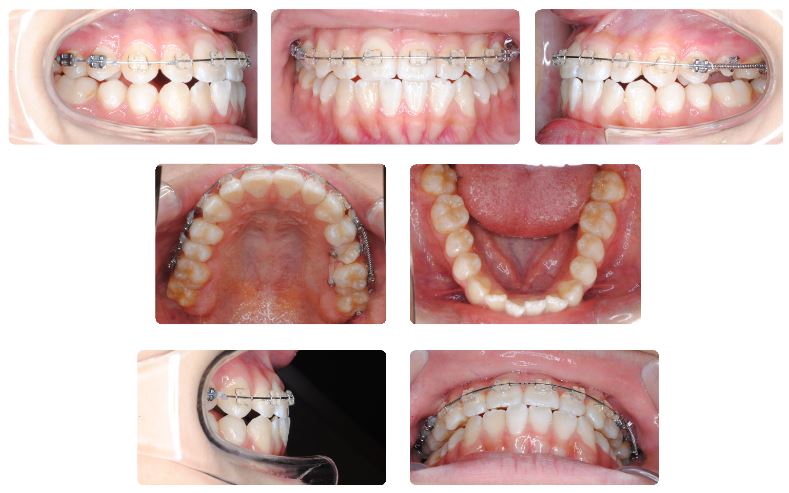

最初の症例は成人男性ですでに前歯の被蓋(前歯の咬み合わせ)はなんとか改善はしておりますが、さらに下顎の側方歯を後方に傾斜させる目的でカリエールモーションを装着することにしました。

下顎用カリエールモーションを装着前の状態です。

上顎前歯が下顎前歯にぶつかり突きあがってしまっている状態です。

このままでは上顎前歯にみられるスペースがなかなか閉じきれないと考えられます。